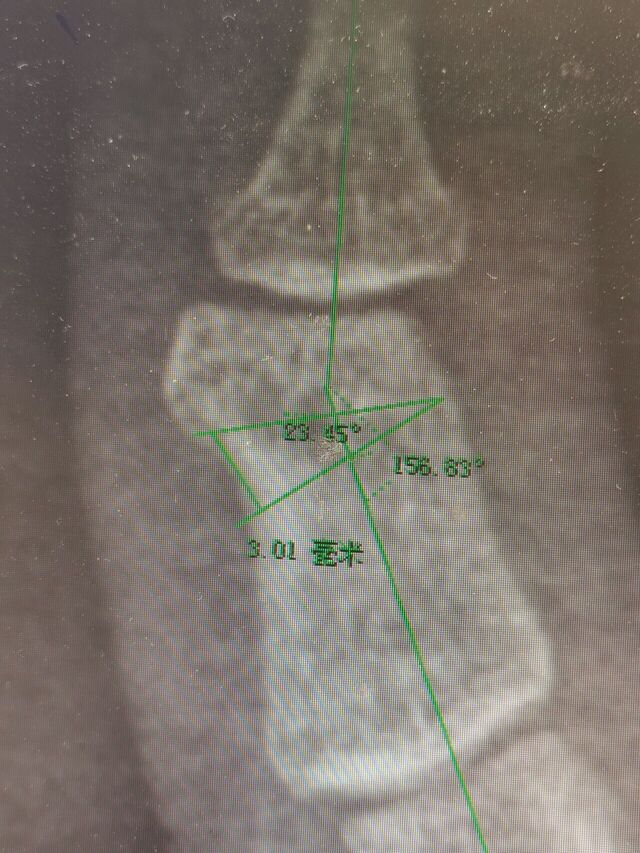

中节指骨宽度10mm厚度4mm

没有合适的截骨摆锯

只能用克氏针并排打孔,然后用骨刀截骨